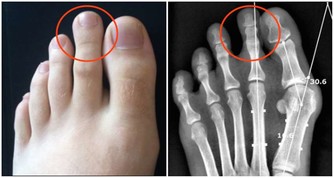

小便泡沫多,半小時都不能消失,說明尿液中排泄的蛋白質較多;

尿液顏色異常,表現為濃茶色、醬油色或混濁如淘米水;

喝水量沒變化的情況下,尿量突然增加或減少,健康人每天排尿次數大約4-6次,尿量約800-2000ml;